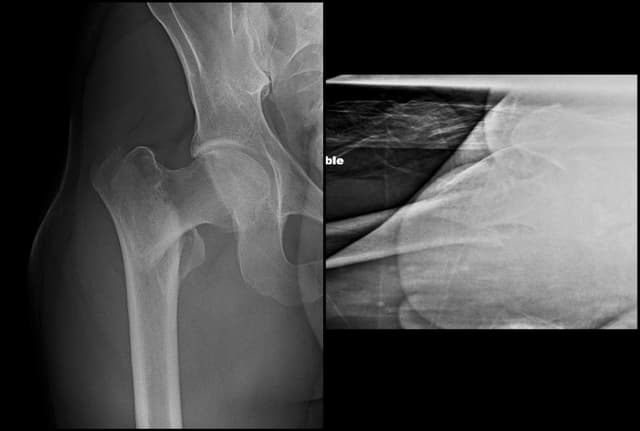

Pre-op